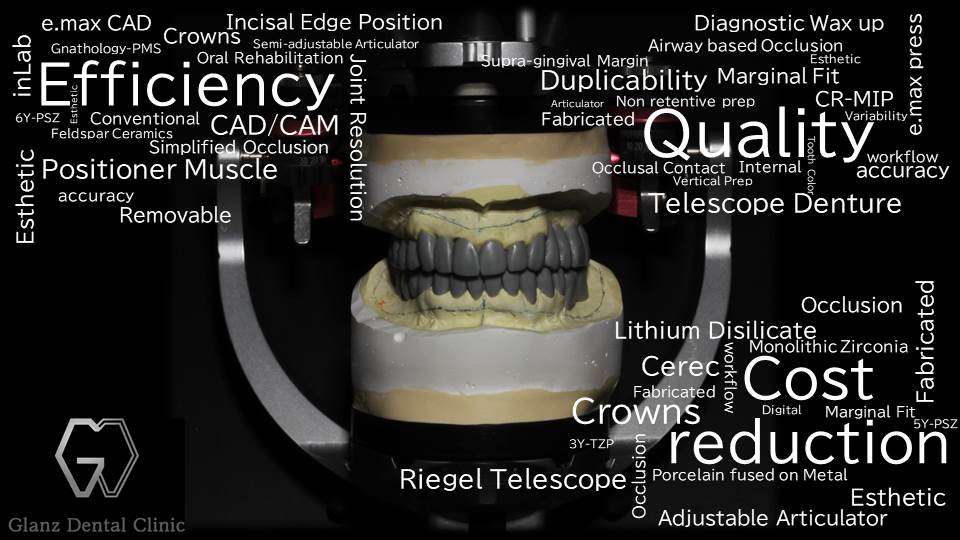

写真の義歯は、総入れ歯の上アゴ部分を覆っているピンクのプラスチックがどうしても違和感が強く、食事の時と外出する時以外は入れ歯を装着出来ていない状態で、通っているお医者さんからの紹介を受けて当院に受診された患者様です。

上顎は「無口蓋型金属床総義歯」で治療をしました。装着して2年目に入られた患者様の例ですが、健康保険適用の入れ歯とは違い、一度得られた歯並び、咬み合わせ、安定感には変化がありません。

※画像の治療は「米国補綴専門医 兼 歯周病専門医」の杉田龍士郎先生の治療です。

●上顎:無口蓋型 金属床 総義歯 約50万円